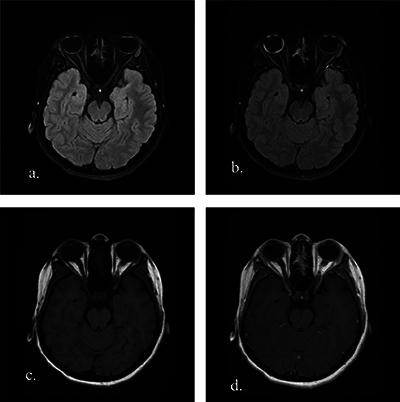

目的:对比增强FLAIR脂肪抑制(CE-FLAIR-FS)成像有可能提高葡萄膜疾病的诊断准确性,并最终提供更好的患者管理。本研究旨在确定 CE-FLAIR-FS 成像与对比增强 T1 加权成像(CE-T1WI)在评估儿童葡萄膜炎患者时的诊断价值。材料和方法:研究回顾性地纳入了21名接受全脑磁共振成像(MRI)(包括CE-FLAIR-FS和CE-T1WI)检查的葡萄膜炎患儿。我们评估了葡萄膜束对比度增强与增厚、玻璃体信号异常以及伴随的脑部异常。与 CE-T1WI 和 CE-FLAIR-FS 图像相比,葡萄膜增强强度被半定量地评估为轻度、中度和明显葡萄膜炎。结果显示全葡萄膜炎(61.9%)是最常见的解剖位置,其中大部分是特发性的(47.6%)。在 42 眼临床葡萄膜炎患者中,21 眼(50%)在 CE-FLAIR-FS 图像上观察到葡萄膜束增强,5 眼(11.9%)在 CE-T1WI 图像上观察到葡萄膜束增强。经检测,CE-FLAIR-FS 对泛葡萄膜炎的灵敏度相当高(80.8%)。CE-FLAIR-FS的受累眼数和增强程度更高(P < 0.001)。在评估葡萄膜炎的严重程度时,CE-FLAIR-FS 的分级明显高于 CE-T1WI,灵敏度更高(P < 0.001,Z:-4.347)。三名患者在 CE-FLAIR-FS 图像上出现玻璃体异常信号,但在 CE-T1WI 图像上却没有。结论CE-FLAIR-FS在诊断小儿葡萄膜炎、确定葡萄膜炎症的累及范围和严重程度以及指导适当的治疗方面发挥着重要作用。将其作为标准序列加入葡萄膜病变的常规核磁共振成像方案将大有裨益。

Objectives: Contrast-enhanced FLAIR fat-suppressed (CE-FLAIR-FS) imaging can potentially increase the diagnostic accuracy of uveal diseases and ultimately provide better patient management. This study aimed to determine the diagnostic value of CE-FLAIR-FS imaging versus contrast-enhanced T1-weighted imaging (CE-T1WI) in the assessment of pediatric patients with uveitis. Material and methods: Twenty-one children with uveitis who underwent whole brain magnetic resonance imaging (MRI), including CE-FLAIR-FS and CE-T1WI, were retrospectively included in the study. We evaluated the presence of uveal tract contrast enhancement with thickening, vitreous humor signal abnormality, and accompanying brain abnormalities. The uveal enhancement intensity was assessed semiquantitatively as mild, moderate, and marked uveitis compared to CE-T1WI and CE-FLAIR-FS images. Results: Panuveitis (61.9%) was the most frequent anatomic location, and most of them were idiopathic (47.6%). Of the 42 eyes with clinical uveitis, enhancement of the uveal tract was observed on CE-FLAIR-FS images in 21 eyes (50%), while in 5 eyes (11.9%) on CE-T1WI. The sensitivity of CE-FLAIR-FS in panuveitis was detected to be quite high (80.8%). The number of affected eyes and enhancement degree were found to be higher on CE-FLAIR-FS (p < 0.001). In assessing the severity of uveitis, CE-FLAIR-FS grades were significantly higher and more sensitive than CE-T1WI (p < 0.001, Z: -4.347). Three patients had vitreous abnormal signals on CE-FLAIR-FS images, but none on CE-T1WI. Conclusion: CE-FLAIR-FS plays a significant role in the diagnosis of pediatric uveitis, identifying the involvement and severity of the uveal inflammation and guiding the appropriate management. It would be beneficial to add it as a standard sequence to the routine MRI protocol for uveal pathologies.